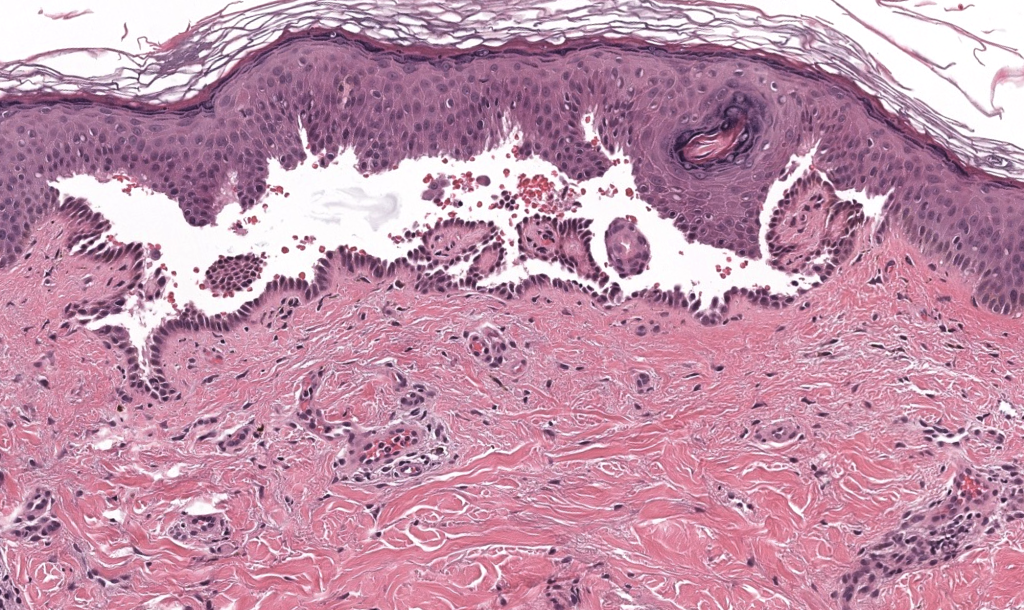

- Histología

- Biopsia de ampolla reciente / borde → ampolla suprabasal + acantólisis + “fila de lápidas”.